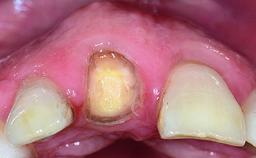

Replacement of a Failing Upper Left Central Incisor: Immediate Placement of an RC Bone Level Implant and Provisionalization

A healthy 23-year-old female patient was referred for a consultation on replacing tooth 21 with an implant-supported restoration. The patient had recently moved to the area and reported a history of endodontic and periodontal treatment for tooth 21. The tooth had been deemed non-restorable by her previous periodontist but since she was going to be moving, he recommended consulting to a dentist in her new city to continue her treatment. A review of her medical history yielded no significant findings and no known drug allergies. The analysis of her smile revealed a medium to high symmetrical smile line and a slightly discolored tooth 21.

Retention Cemented, with prosthesis margin < 3mm submucosal Cemented, with prosthesis margin < 3mm submucosal

Provisional Implant-Supported Prosthesis Prosthodontic margin < 3 mm apical to mucosal margin Prosthodontic margin < 3 mm apical to mucosal margin